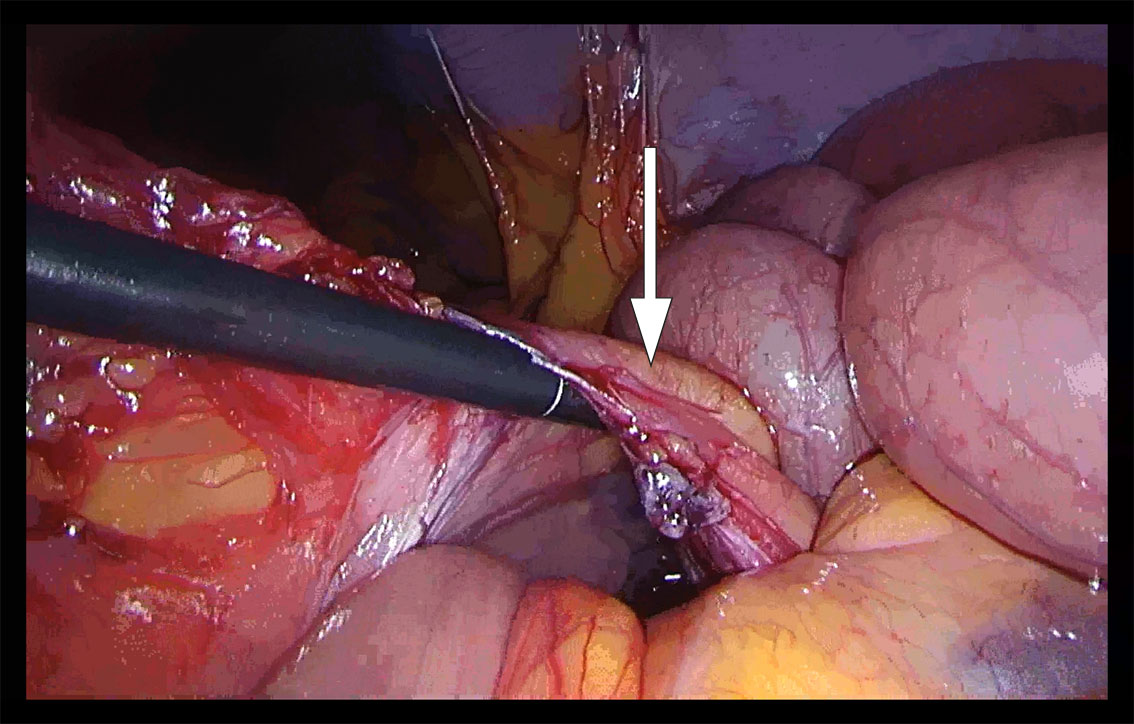

I generell anestesi fant vi ved laparoskopi sparsom fri væske i bukhulen. Store deler av tynntarmen var dilatert. Vi begynte å reponere tynntarmen mot høyre, først fra proksimalt mot distalt og deretter fra ileocøkalovergangen mot proksimalt. Vi fikk inntrykk av at tynntarmen var herniert innunder en «streng» i tilknytning til venstre colon. Ved nærmere ettersyn kunne man skimte vaskulære strukturer, og et tynt og defekt mesenterium kunne ikke utelukkes (figur 1). Grunnet mye dilatert tarm i feltet, begrensede plassforhold og usikkerhet om hvorvidt all tarm var reponert, valgte vi å konvertere til laparotomi. Med midtlinjetilgang fant vi mekanisk tynntarmsileus fra en venstresidig paraduodenal herniering med store deler av tynntarmen herniert mot venstre dorsalt for vena mesenterica inferior. Tynntarmen som ble reponert, framsto som viabel, da det var god tarmmotilitet og god blodsirkulasjon. Det ble satt fortløpende suturer med patent lukning av åpningen i mesenteriet, uten skade av karstrukturene.

Ved regranskning av pasientens CT-bilder forløp v. mesenterica inferior ventralt for de hernierte tynntarmsslyngene. Dette ble også sett peroperativt og samsvarte med diagnosen paraduodenalt brokk (figur 2)